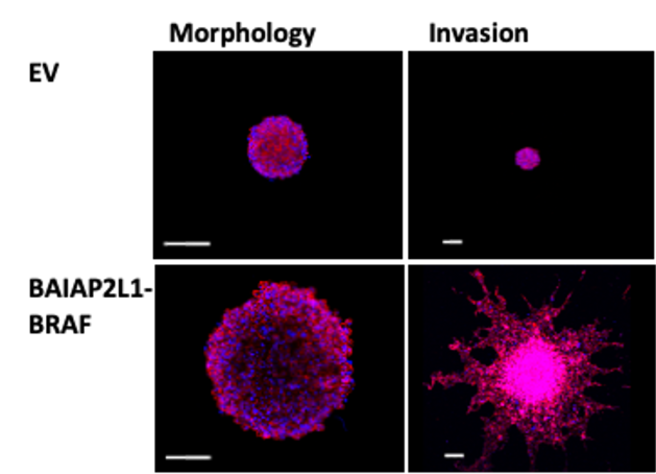

In a recent study from our lab, we discovered in a patient with papillary thyroid carcinoma (PTC) a novel rearrangement leading to a BAIAP2L1-BRAF fusion, and whose transforming ability we have demonstrated. Furthermore, our integrative multiomics analysis of a cohort of PTC patients has uncovered additional druggable candidates, which seem to be more common targets, since the observed deregulation is independent of the underlying oncogenic mutation. Our multiomics analysis demonstrates how new targets can be identified, which in turn might have the potential to advance the field of precision medicine.